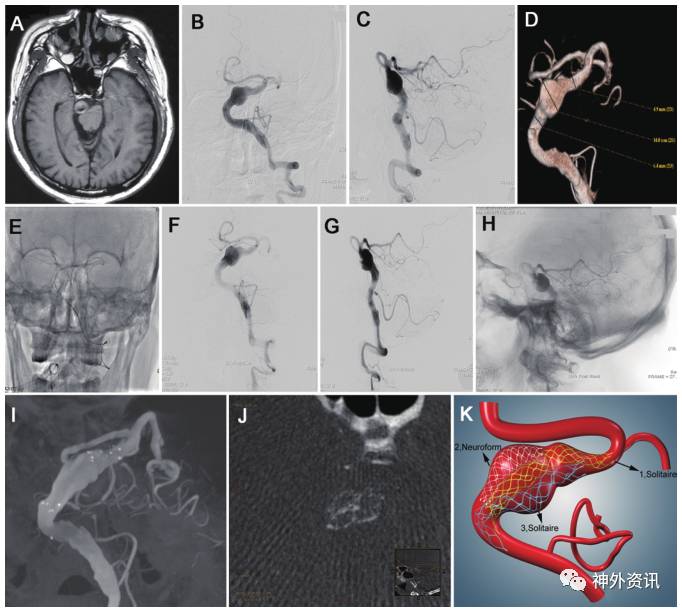

图1. 64岁男性VFA患者,表现为头痛、头晕和耳鸣。A.头颅MRI显示脑干区的巨大VFA,压迫脑干;B、C.术前DSA的正位和侧位片提示,左侧椎基底动脉主干部位巨大梭形动脉瘤;D.3D CTA显示最大径14mm的巨大VFA;E.DSA示置入3个支架至VFA:Solitaire 6×30 mm、Neuroform 4.5×30mm和Solitaire 6×30mm;F、G、H.术前DSA结果;I、J.支架植入后正位和轴位DSA成像结果;K.平行支架置入后的示意图。